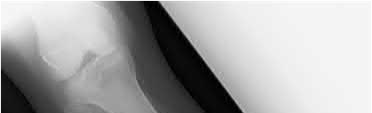

Figure B demonstrates an isolated medial femoral condyle fracture. Lateral locked plating is not an appropriate technique for this fracture.

The fracture shown in Figure B is an AO B type (partial articular fracture). This fracture is best treated with open reduction internal fixation through a medial approach, with lag screw and buttress plate fixation.

Figures A, C, D and E show supracondylar distal femur fractures that can be treated with ORIF with a fixed-angle device such as lateral locked plating.